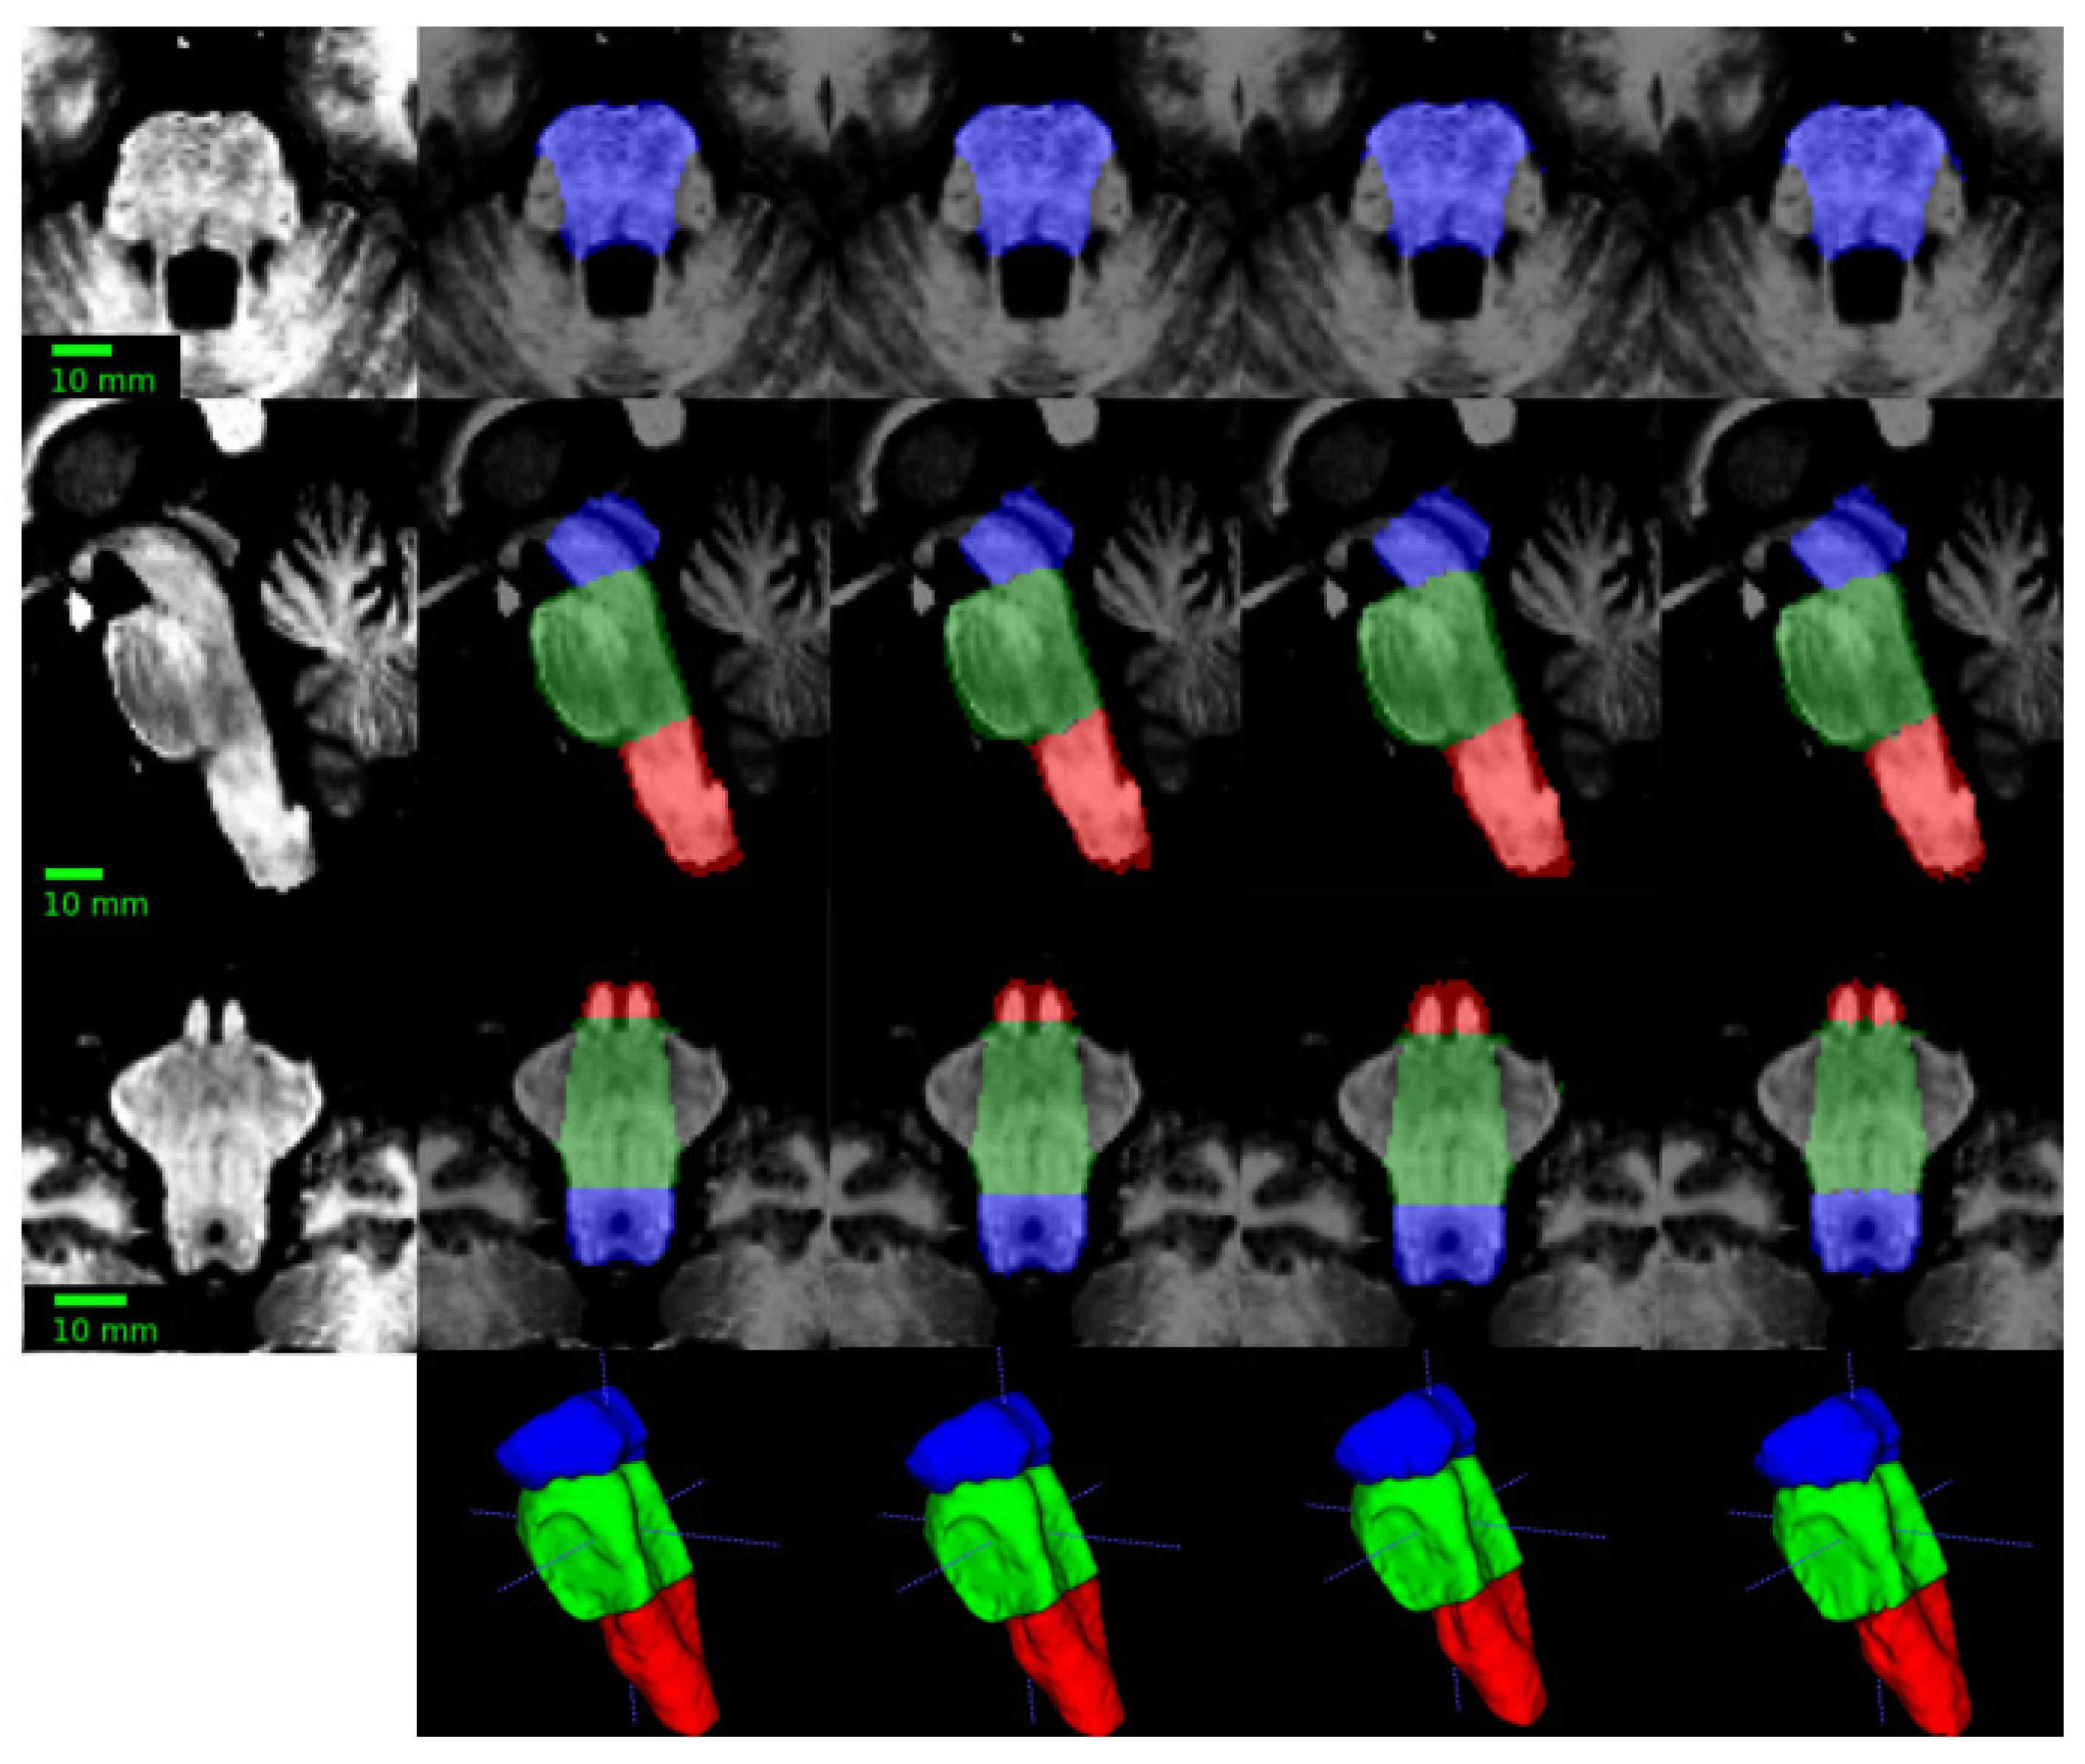

- Superior Segmentation Performance: The proposed modified U-Net architecture (with attention-enhanced skip connections and inception modules) significantly outperforms three comparative approaches in brainstem parcellation, achieving higher Dice scores across all substructures (medulla, pons, mesencephalon) and the whole brainstem.

- Volume Differences Across Groups: Automated segmentation reveals distinct volumetric patterns, with controls exhibiting larger volumes (whole brainstem: 1.62) compared to preclinical (1.49) and patient groups (1.12), suggesting potential atrophy linked to disease progression.

- Clinical Utility: The method’s accuracy and robustness support its potential for precise brainstem assessment in neurodegenerative disorders, enabling earlier detection of structural changes (e.g., reduced medulla volume in patients: 0.26 vs. 0.31 in controls).

| Mesencephalon | 0.96±0.022 | 0.91±0.023 | 0.93±0.019 | 0.89±0.031 |

| Pons | 0.96±0.015 | 0.93±0.016 | 0.94±0.013 | 0.91±0.029 |

| Medulla | 0.95±0.021 | 0.91±0.022 | 0.92±0.021 | 0.91±0.023 |

| Full brainstem | 0.96±0.008 | 0.94±0.008 | 0.95±0.007 | 0.93±0.013 |

| Brainstem section | Mean volumes (% TICV) | P | ||

| Patients | Preclinical | Controls | ||

| Mesencephalon | 0.4 | 0.44 | 0.48 | 0.007 |

| Pons | 0.47 | 0.76 | 0.82 | < 0.0001 |

| Medulla | 0.26 | 0.29 | 0.31 | 0.00012 |

| Whole brainstem | 1.12 | 1.49 | 1.62 | < 0.0001 |